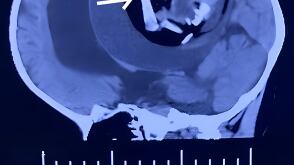

Exames identificaram o feto

A partir de uma ressonância foi possível observar que uma ‘cápsula’ de defesa foi formada ao redor do feto pelo corpo da bebê. A principio, os profissionais acharam que se tratava de um grande tumor. Contudo, outros exames mostraram a presença de ossos, revelando ser um feto com má formação.